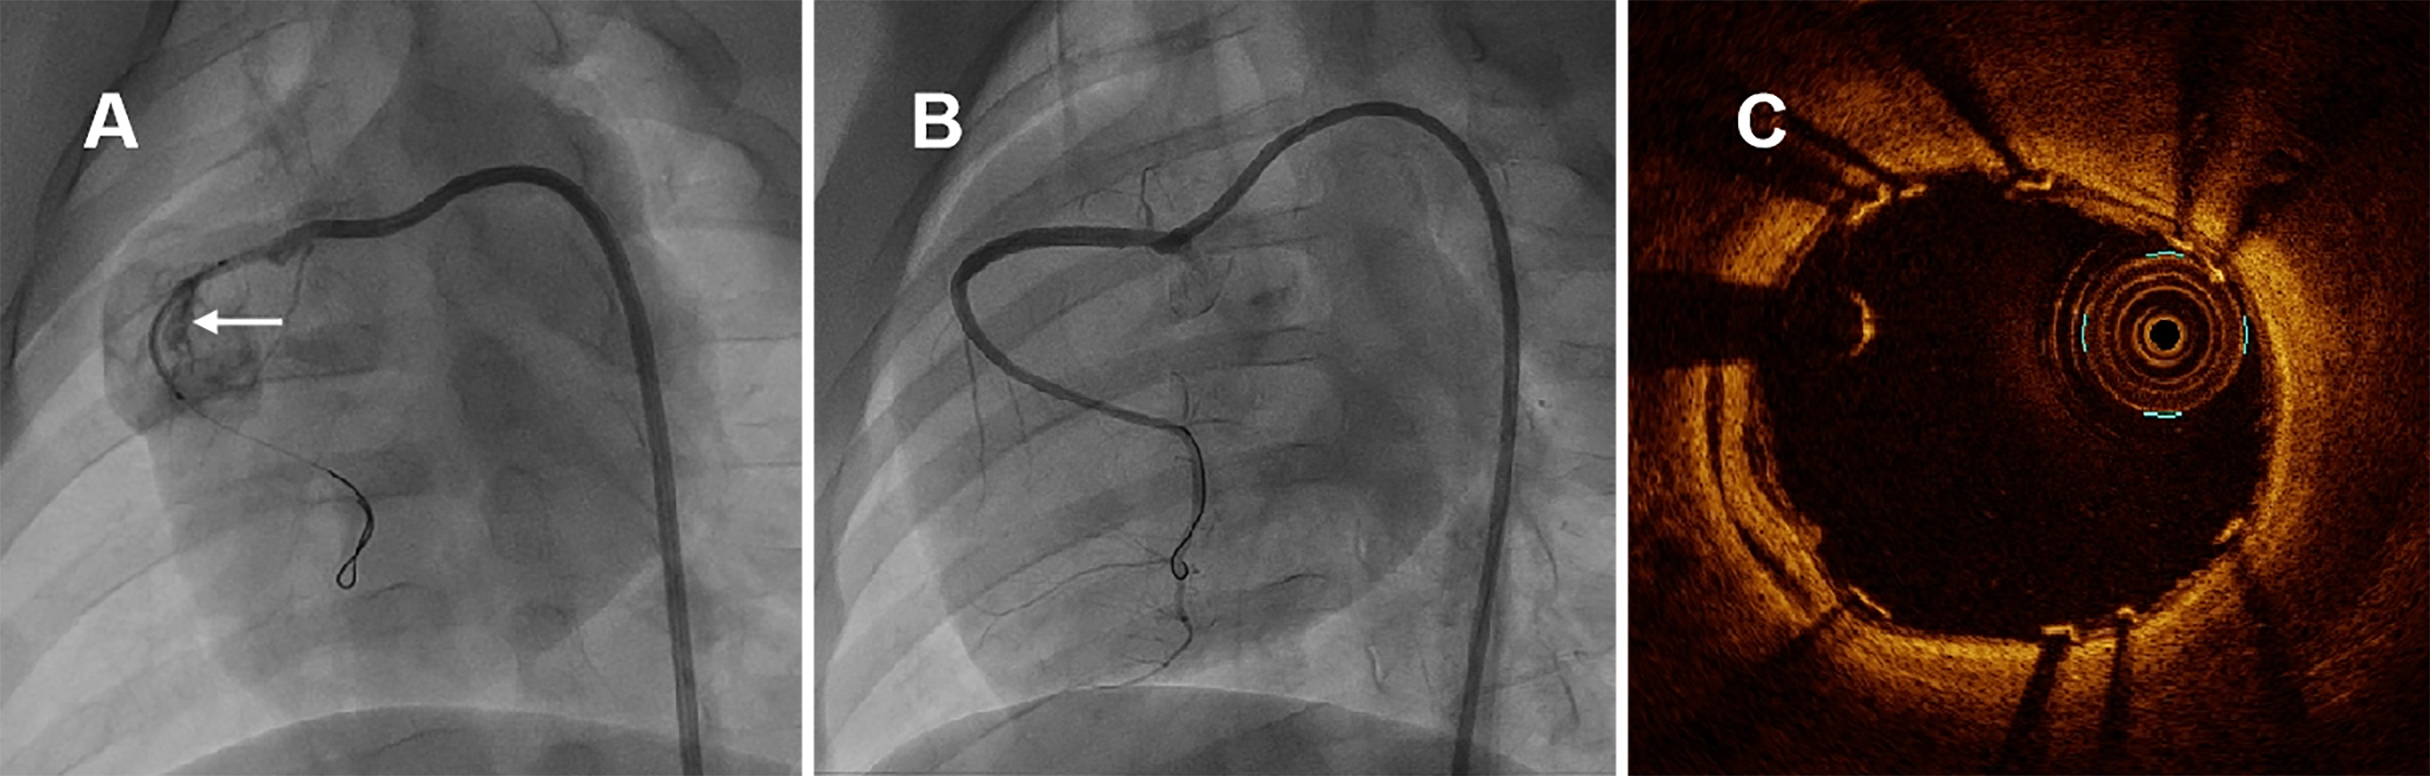

Subsequently, self-made covered stent was deployed to seal the breach of RCA, shown in Fig. 2A. Finally, CAG and OCT examinations were performed immediately after stent implantation. When ventricular arrhythmia happened, electrical defibrillation, cardiopulmonary resuscitation and drug therapy were carried out. The swines were allowed to recover and resume feeding for subsequent study.

Fig. 2.Representative coronary angiographies and OCT image in swine immediately after covered stenting. (A) Coronary artery perforation was induced by non-compliant balloon burst and self-made covered stent was positioned in RCA, the white arrow indicated the perforation of coronary nature architecture. (B) CAG of RCA immediately after covered stenting. (C) OCT examination immediately after covered stenting. CAG and OCT examination revealed that the new covered stent was sufficient expansion without malapposition, meanwhile with pretty blood flaw. OCT, optical coherence tomography; RCA, right coronary artery; CAG, coronary angiography.

A total of seven juvenile Yorkshire swines were used for this study. One swine suffered from ventricular fibrillation during the OCT examination immediately after stent implantation and survived by electrical defibrillation. Two swines were euthanasia at 14 days and 28 days after procedure, respectively. The remaining 5 were sacrificed at six months. During coronary artery injury in RCA induced by balloon burst, no hemodynamic disorder had been detected in these animals during the procedure. Angiographic and OCT examinations immediately after stent implantation showed that the self-made covered stent had completely sealed the breach segment, achieving good apposition of the stent to vessel wall, as well as pretty antegrade blood flaw-thrombolysis in myocardial infarction (TIMI) grade 3, shown in Fig. 2B,C.